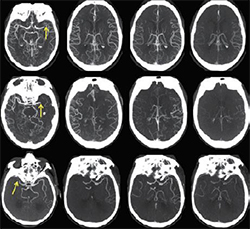

従来の3D回転撮影は,左右方向の一定軌道回転のみだったため,コーンビームCT特有のアーチファクトが生じていた。ARTIS iconoは回転撮影中に頭尾方向の傾斜を加えた独自の二重軌道回転機構により,多方向のスキャンデータによる3D画像再構成が可能になった。骨構造近くの出血などの描出能も向上し,さらなる高画質CTライクイメージングを提供する。

・syngo DynaCT Multiphase

脳実質の血液量分布評価のみだったCTライクイメージングによる3D機能画像に,時間軸情報が追加され,血流評価が可能になった。急性虚血性脳卒中の側副血行動態確認を血管撮影室でも行え,脳梗塞か脳出血かを瞬時に判断できるため,診断から治療への迅速なワークフローを実現する。